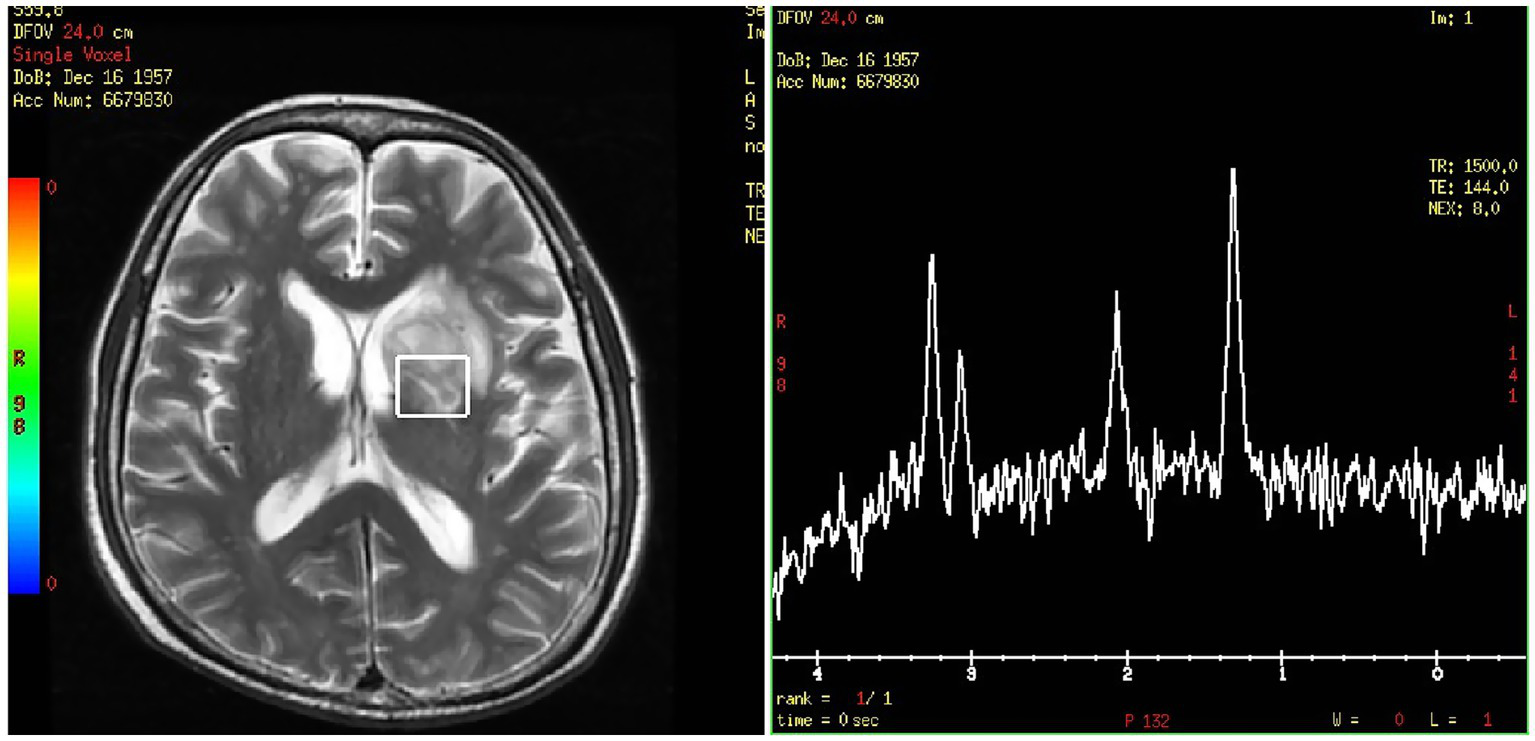

Figure 3

Brain magnetic resonance spectroscopy of the left basal ganglia.

On day 24, the patient presented with transient amnesia of recent events and one episode of fecal incontinence. Physical examination revealed a decline in functions of temporal and spatial orientation. The Glasgow Coma Scale score was 14 (E4V4M6). A brain MRI (Figure 2C1) was performed, which revealed a 39 × 28.9 mm mass in the left basal ganglia and new infarction foci in the left cerebral peduncle and the right cerebellar hemisphere. Moreover, another abdominal CT (Figure 2A2) scan revealed multiple new, rounded, low-density lesions in the spleen compared with the results of previous abdominal CT scan before chemotherapy, which suggested new splenic infarctions. However, no significant evidence of lymphoma progression was observed. On day 27, the patient experienced in continence of urine and feces again and concurrently answered incorrectly about his age. A subsequent chest CT scan revealed progression of the right lower lung lesion (Figure 2B2). A second brain MRI scan revealed an increased size of the mass in the left basal ganglia (Figure 2C2). Lumbar puncture was performed and normal cerebrospinal fluid (CSF) pressure was observed. Results of bacterial culture and mNGS test of CSF were negative. At the same time, we reexamined mNGS analysis of his peripheral blood sample, and no reads of Rhizomucor species were detected. On day 37, brain magnetic resonance spectroscopy (Figure 3) was conducted, indicating that the lesion in the left basal ganglia was nonneoplastic. After a discussion among experts in multiple disciplines, they agreed that the newly developed lesions in the lungs, CNS, and spleen were consistent with organ artery invasion by Mucor fungi and/or fungal emboli caused by Rhizomucor infection.